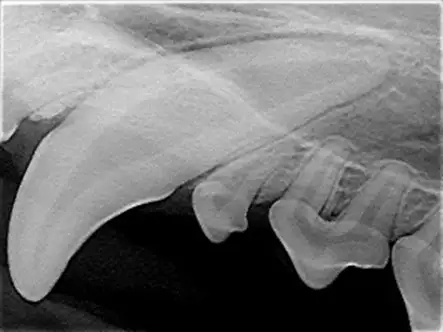

Species Considerations

In cats, canine teeth are nearly cylindrical (root is not wider; A), so simple elevation may be sufficient, particularly if the tooth is already mobile due to chronic alveolitis or osteitis in older cats. In these cats, the gingiva may be very thin, making full-thickness mucoperiosteal flap creation challenging. In most dogs, however, the diameter and width of the root is broader than the widest part of the crown at the neck of the tooth, with a larger dimension from front to back (mesial to distal) than side to side (buccal to palatal; B). A full-thickness pedicle mucogingival flap with alveolar bone removal is recommended for both species but is more critical in dogs.

A